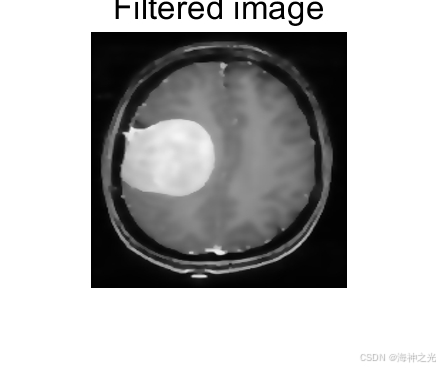

⛄一、各向异性扩散滤波器大脑MRI图像肿瘤识别

2 MRI肿瘤识别流程

1. 预处理阶段

各向异性扩散用于去噪,抑制MRI中的Rician噪声。通过多次迭代调整扩散系数,在均匀区域平滑噪声,在肿瘤边缘(高梯度区域)停止扩散。

2. 特征增强

滤波后的图像通过梯度幅值或Hessian矩阵进一步突出肿瘤边界。例如: